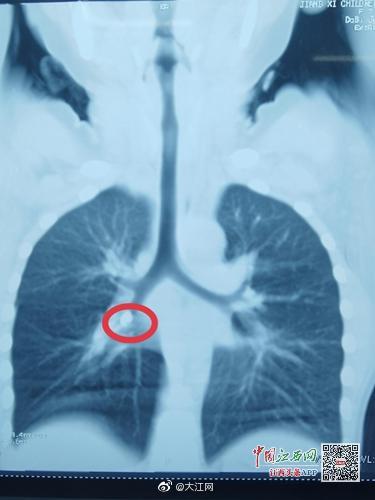

大江快報(bào) 【江西7歲男孩咳嗽不止 原來是門牙嗆入了氣管】近日,江西省兒童醫(yī)院接診了一名特殊的患者,7歲的小巖換牙后一直被咳嗽所困擾,怎么治都不見好。經(jīng)檢查,發(fā)現(xiàn)小巖支氣管內(nèi)有異物,醫(yī)生取出后才發(fā)現(xiàn)異物竟然是一顆牙齒。 上饒市橫峰縣的小巖今年7歲了,正是換牙的年齡,兩顆“門牙”已經(jīng)脫落一顆,還有一顆搖搖欲墜。小巖吃東西時(shí)候門牙處疼痛不適,家屬心疼不已,和小巖商量把搖搖欲墜的牙齒拔掉。不過,在家屬徒手拔下牙齒后,孩子疼痛難受,哭吵起來,慌忙間家屬手上的牙齒掉到嘴巴里面。小巖當(dāng)即出現(xiàn)劇烈咳嗽、顏面發(fā)紺,家屬給予拍背后逐漸緩解,持續(xù)1分鐘咳嗽緩解。家屬以為是口水嗆了,牙齒被吃進(jìn)肚子內(nèi),未引起重視。